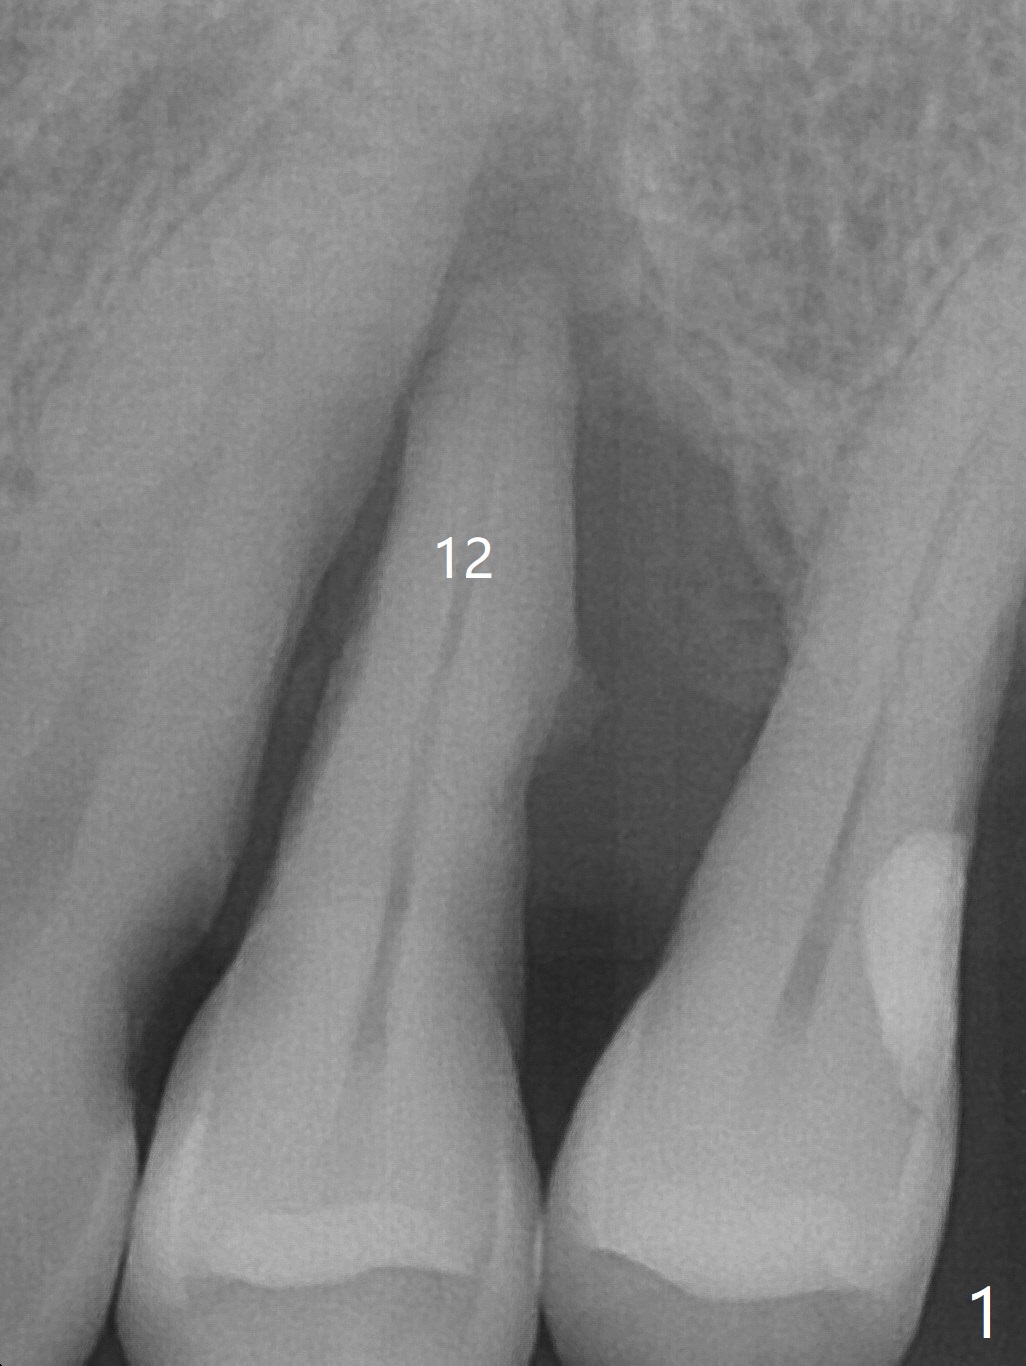

A 55-year-old man has been our patient intermittently for the last 15 years. Before removal of the tooth #12 with loss of the buccal plate (Fig.1), he requests bone graft for the health (strength) of the neighboring teeth (Fig.2 *). To keep the 6-month membrane in place longer, periodontal glue is used after suturing (Fig.3 (blue)). There is buccal collapse 2 months post socket preservation (Fig.4,5). Titanium mesh or Cytoplast should have been placed.